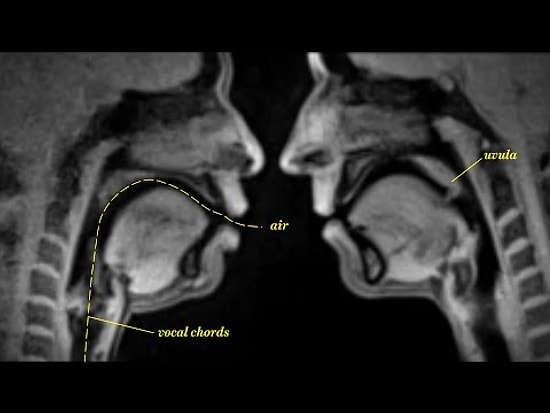

Gebelikte Cinsellik

Bebek bekleyen çiftler hamileliğin getirdiği heyecan ve coşkuyu yaşarken bebeklerini ve kendilerini bekleyen sürece dair yüzlerce soru sorarken, genelde bilmedikleri ve utandıkları için doktorlarına soramadıkları bir soru ile karşı karşıya kalırlar;Gebelikle beraber cinsellik sonlandırılmalı mıdır, yoksa cinsel hayatın devamı  mümkün müdür?Özellikle cinsellik konusunda bilgilendirme soru sormaya bile çekindiğimiz  bizimki gibi toplumlarda gebelik sürecinde  cinselliği konuşmak daha da zor bir hal almakta ve bu da bilginin, yerini yanlış inançlar  ve asılsız korkulara bırakmasına neden olmaktadır. Gebelik dönemi kadın hayatının en karmaşık dönemlerinden biridir. Hamilelik psikolojik ve fiziksel birçok değişimin olduğu bir dönemdir. Bununla beraber yaşanan bu sürece uyum adına yapılanların, yanlış bilgilenmeler yüzünden,  bebeği korumak uğruna korkuların takıntı halini alması doğru ve açık bilgilendirme ile engellenebilir. Burada hekim-hasta ilişkisinin açık, samimi ve anlaşılır şekilde kurulması bebek bekleyen çifti rahatlatacağı gibi anne karnındaki  bebek için her koşulda en doğrunun yapılabilmesine olanak sağlayacaktır.Anne- baba adaylarının en sık merak ettiği sorular ve cevapları şunlardır;-Hamileliğin ilk aylarında cinsel ilişki düşüğe neden olur mu?Hayır. Hamileliliğin ilk dönemlerinde başka bir tıbbi sorundan kaynaklanan düşük tehdidi söz konusu değilse cinsel ilişkinin düşüğe yol açması söz konusu değildir. Yapılan çalışmalarda başka nedenlere bağlı olarak düşük tehdidi olmayan kadınların cinsel ilişkiye girmesinin düşük olasılığını artırmadığı kanıtlanmıştır.-Gebelikte cinsel istek azalır mı?Gebeliğin ilk üç ayında anne adayında genel olarak bir halsizlik, uyku hali, mide bulantısı mevcuttur. Özellikle kokulara karşı artmış hassasiyet bile cinsel isteği olumsuz etkileyebilir. Bu agresif değişimler anne adayının cinsellikten uzaklaşmasına ve isteksizliğine neden olabilmektedir. Bu çok doğal ve aynı zamanda geçici bir süreçtir. Gebeliğin ilk üç ayından sonra normale döner. Anne adaylarının çok az bir kısmında bu isteksizlik altta yatan başka nedenlere bağlı olarak devam edebilir. Bu durumlarda çiftlerin birbirine açık, yardımcı ve anlayışlı olması sürecin daha kolay geçirilebilmesini sağlamaktadır.-Orgazm olmak bebeğe zarar verir mi?Bu konuda yanlış bilgilenmelerden biri de orgazm olmanın bebek ya da anne sağlığı açısından bir risk teşkil edebileceği düşüncesidir. Orgazmın kadın vücudunda nelere sebep olduğu uzun yıllardır bilinen bir gerçek. Bununla beraber, yine uzun zamandır gebe kadınların orgazm yaşamaları sırasında ve sonrasında bedeninde oluşan değişiklikler bilimsel açıdan bilinmektedir. Gebe kadının orgazm olmasının bebeğe ya da kendine hiçbir zararı yoktur. Orgazm sonrası genel bir rahatlamadan sorumlu olan endorfin salgısının, bebeğin de yararına olduğu da bir gerçektir. Bu nedenle cinselliği hem en istekli hem de en rahat yaşayabileceğiniz ikinci üç aylarda bu konuda çok rahat olabilirsiniz.-Gebelikte cinsel ilişki erken doğuma neden olur mu?Cinsel ilişkinin erken doğuma neden olabileceği de sıkça karşılaşılan bir düşüncedir. Ancak genel kanının aksine cinsel ilişki varlığı ya da sayısının erken doğumla bir ilişkisi saptanmamıştır. Gebeliğin doğuma yakın zamanlarında da cinsel ilişkiye girilebilir. Genel olarak erkek ejekulat sıvısındaki prostoglandinlerin artık olgunlaşmış ve reseptörleri gelişmiş olan rahimde hafif  kasılmalara yol açabileceği bilinmelidir. Bunlar geçici kasılmalardır ve normal seyreden bir gebelikte bebeğe bir zararı olmaz. Fakat özellikle son üç ay doğumun yaklaşması nedeniyle kadında beliren doğum korkusu, endişe ve heyecan  bu kasılmalar nedeniyle artabilir.Eğer anne adayının cinsel ilişkiye girmesine engel bir problemi varsa ya da yüksek riskli bir gebelik mevcutsa bu durum takipleriniz esnasında hekiminiz tarafından size zaten bildirilecektir. Bütün bunlardan önemlisi  gebenin kendi durumu hakkında hekimden bilgi alması ve gebelikte yapabileceklerini dair doğru bilgileri edinmesidir. Herhangi bir tıbbi probleminiz bulunmadığı koşullarda cinsellik yaşamaktan çekinmenize hiçbir neden bulunmamaktadır. Gebelik,  kadın olarak yaşayabileceğiniz en güzel ve eşsiz deneyimdir. Bu güzel döneminizde cinselliğinizi de sınırlamanız gerekmez.